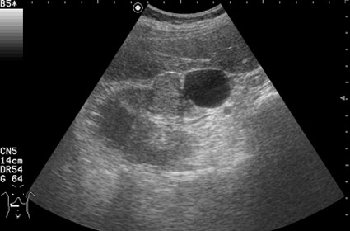

- Поперечное серошкальное сканирование.

Как трактовать выявленные изменения? Какова тактика врача УЗД в данной ситуации?

Вас не смущает наличие внутреннего кровотока в одной из "кист"?

Обозначенный сегмент почки по структуре не отличим от рядом лежащих участков, выбухание контура над указанным сегментом тоже ни о чем не говорит, т.к. может быть просто дольчатостью.

Дольчатость почки в 56 лет?

При гистологии эта структура была почечно-клеточным раком (RCC).